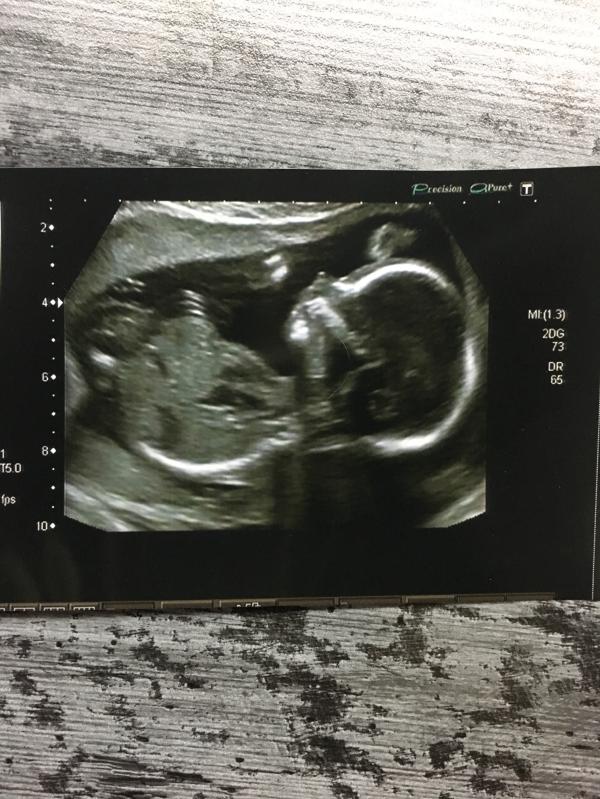

Была сегодня на втором скрининге - и вот вам мой пузожитель! У него/неё все хорошо! И водичка чистая, и плацента крепкая! Во время нашего с ним/ней знакомства облизывался/лась и махал/а ножками! Судя по фото - будет очередная копия папы... но я не теряю надежды! А почему я не говорю пол?! Да я его и сама не знаю! Решили поддаться новому веянию «моды» и сделать себе «сладкую» интригу! В общем будем кушать вкуснючий торт от @apelsinka_klg, в вскр. Я вам его, конечно же, покажу.... но что-то мне п...